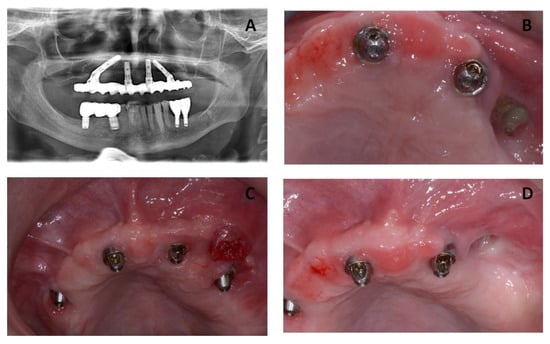

The patient underwent three surgeries in total. The first surgery was scheduled for September 2016 and included removal of the necrotic bone and implant #26 (Figure 2). After a healing period of three months, the All-on-4 prosthesis was placed for function and esthetics.

The second surgical session in October 2016 included the removal of implant #46 and the osteonecrosis lesion on the posterior right side of the mandibular bone (Figure 3).

Figure 2. (A,B) Intra-operative image from the patient showing removal of the maxillary dental implants and osteonecrotic lesion. (C) Intra-oral post-operative view of the patient after a month showing healthy tissues. (D) The radiographic image shows the post-operative situation with the previous prosthesis adjusted to the new situation.